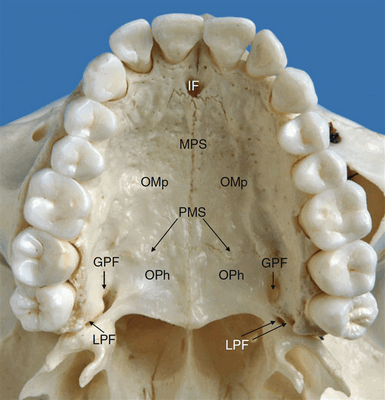

Твёрдое и мягкое нёбо в комплексе формируют крышу полости рта и дно полости носа (Рисунок 1 и 2). U-образная зубная дуга является передней и боковой границей твердого нёба, в то время как свободный край мягкого неба ограничивает нёбо сзади. Передние ¾ твердого неба представляют собой нёбный отросток верхней челюсти, оставшаяся четверть – это горизонтальная пластинка нёбной кости. Правая и левая половины нёба посередине соединяются посредством срединного нёбного шва. Нёбные отростки верхних челюстей соединяются с горизонтальными пластинками нёбных костей с помощью нёбноверхнечелюстного шва (Рисунок 3). В области твердого нёба расположен ряд клинически определяемых образований, например нёбное отверстие носонёбного канала, так называемое резцовое отверстие, а также большое малое резцовые отверстия, которые рассматриваются в этой статье. Кости твердого нёба испещрены отверстиями каналов питающих сосудов и углублениями, в которых лежат малые нёбные слюнные железы (du Toit и Nortjé 2003). Твердое небо покрыто жевательной слизистой, которая формирует поперечные складки переднем отделе нёба. По средней линии нёба проходит слегка приподнятая над окружающими тканями продольная мягкотканная полоса – нёбный шов. Эта полоса доходит до резцового сосочка, который находится в проекции резцового отверстия.

Рисунок 3 Сухой препарат черепа, вид снизу на твёрдое нёбо. GPF – большое нёбное отверстие; IF – резцовое отверстие; LPF – малое нёбное отверстие; MPS – срединный нёбный шов; OMp – нёбный отросток верхней челюсти; OPh – горизонтальная пластинка нёбной кости; PMS – нёбноверхнечелюстной шов